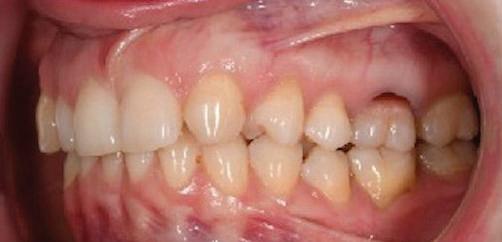

Dental Tribune Bulgarian Edition / октомври 2022 г.16 клиничен случай с алайнери Г орният латерален ре зец е вторият найчесто вродено липсващ зъб.1,2 Поради разполо жението му във видимата зона на усмивката лечение то на подобни случаи нала га мултидисциплинарен под ход, целящ отличен функцио нален и естетичен резултат. Налице са няколко лечебни мо далности, свързани с различ но разпределение на място то: първият вариант е орто донтско отваряне на място и възстановяване на липсва щия зъб с конструкция, под държана от съседните зъби3 или от имплант4, докато при втория подход разстоянията се затварят и премоларът заема мястото на канина.5 Изборът на лечебен подход трябва да бъде направен съв местно от зъболекар и паци ент въз основа на очакванията на последния и предвиди мостта на лечението. Множе ство фактори влияят върху това решение, като напри мер типа малоклузия, размера, формата и цвета на кучеш ките зъби6, оклузалните вза имоотношения (овърджет и овърбайт), лицевия профил, дължината на зъбната дъга и несъответствията в разме ра на зъбите.7 В настоящата публикация се разглежда случаят на жена в зряла възраст с вродена лип са на горен ляв латерален резец. Бяха приложени про зрачни алайнери за отваряне на място за единичен им плант и бяха постигна ти функционална оклузия и отлична естетика. ПРЕДСТАВЯНЕ НА СЛУЧАЯ Диагноза Пациентката бе на 32 годи ни, когато лечението започна, и първоначалното ѝ състоя ние бе следното (фиг. 1–3): липсващ горен ляв латерален резец; клас II, подклас I малоклузия; отклонение на горната сре динна линия вляво; Доклад на клиничен случай ЛЕЧЕНИЕ С АЛАЙНЕРИ НА ПАЦИЕНТ С АГЕНЕЗИЯ НА ЛАТЕРАЛЕН РЕЗЕЦ Д-р Iro Eleftheriadi и д-р Christodoulos Laspos, Гърция и Кипър Фиг. 1a–h Предоперативни лицеви и интраорални снимки. Фиг. 2a–e Дигитални модели преди началото на лечението. Фиг. 3 Панорамна снимка преди лечението. Фиг. 1a Фиг. 1d Фиг. 1f Фиг. 2a Фиг. 2d Фиг. 2b Фиг. 2e Фиг. 3 Фиг. 2c Фиг. 1b Фиг. 1e Фиг. 1g Фиг. 1h Фиг. 1c

Dental Tribune Bulgarian Edition / октомври 2022 г. 17клиничен случай с алайнери леко струпване в долната че люст; несъответствие по Болтън (мандибуларен излишък от 3.06 мм във фронталната зона и общо 1.47 мм); издължено лице с лицева аси метрия; конвексен профил с ретруди рана долна челюст и проми нентен нос. На мястото на зъб #46 бе на лице имплант, а зъби #16 и 26 са ендодонтски лекувани. Тези зъби бяха асимптоматич ни, затова бе взето решение да се прави релечение само при нужда. Мъдреците липсваха. Анализът на телерентгеногра фията (фиг. 4) показа ретрог натна мандибула (SNB: 74.2°) и нормална инклинация на резците както в

Цели на лечението и лечебен план Целите на лечението бяха следните: нивелиране и подреждане на зъбите и в двете зъбни дъги; отваряне на пространство за липсващия латерален резец; коригиране на отношенията при канините и моларите до клас I; и корекция на отклонението на срединната линия. Лечебният план включваше: корекция на отношенията при кучешките зъби и мола рите до клас I с дистализира не на максилата; отваряне на пространство в областта на #22 за поставя не на единичен имплант; корекция на срединната ли ния; и създаване на място за раз ширяване на зъб #12 и апрок симална редукция в долната челюст с цел подобряване на несъответствието по Болтън и осигуряване на подобра оклузия. Изпълнение на лечебния план Този случай бе изпълнен със системата за алайнери Invisalign (Align Technology). Одобреният първоначален лечебен план предвиждаше 49 алайне ра с дистализиране на задни те горни зъби до клас I (прибли зително с около 3.5 мм; фиг. 5). За бъдещия имплант в областта на липсващия латерал бе планирано пространство от 6.5 мм, докато във фронталния сегмент на долната челюст бе предвидена апроксимална редук ция. В дясната страна бутон за ластици клас II бе поставен на зъб #47 вместо на зъб #46, за да не се увреди короната на импланта. Понеже пациентката жи вееше в чужбина,

следните казуси: недобра оклу зия в дисталните зони по вре ме на дистализирането на гор ната челюст и накланяне на зъб #21 (фиг. 7). Последното се дължи на липсата на компози тен атачмънт на този зъб, каквото не бе зададено в пър Фиг. 4 Телерентгенография и цефалометричен анализ преди началото на лечението. Фиг. 5a–e Одобреният първоначален лечебен план. Фиг. 6a–h Снимки по време на лечението, показващи нуждата от внасяне на някои корекции. Фиг. 4 Фиг. 5a Фиг. 5d Фиг. 6a Фиг. 6d Фиг. 6f Фиг. 6b Фиг. 6e Фиг. 6g Фиг. 6h Фиг. 6c Фиг. 5e Фиг. 5b Фиг. 5c

Dental Tribune Bulgarian Edition / октомври 2022 г.18 воначалния план. Тези пробле ми бяха адресирани чрез допъл нителна поръчка на алайнери с торк контрол и зададено екст рудиране на задните зъби с цел установяване на добри оклузал ни контакти в дисталните об ласти, като бяха предвидени и оптимизирани атачмънти с контрол над корените за корекция на ангулацията на макси ларните резци (фиг. 8). Резултати от лечението Панорамната рентгено графия след ортодонтското лечение показа благоприятна паралелна позиция на съседни те зъби, подходяща за поставя не на имплант в областта на #22, както и конвергенция на ко рените на зъби #44 и 45 (фиг. 9), но преценихме, че няма да от деляме допълнително лечебно време за коригирането ѝ поради факта, че пациентката бе мно го доволна от постигнатия до момента резултат. След при ключване на лечението бяха постигнати отлични взаимо отношения клас I при мола рите и канините, а срединни

съвпадаха. Върху им

планта бе поставена временна коронка (фиг. 10 и 11), докато бъде изготвена окончателна та. Бе постигнат отличен кра ен резултат. Меките тъка ни около импланта напълно заздравяха, което доприне се за перфектната хармония между бяла и розова естетика (фиг. 12–15).